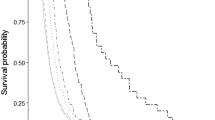

The outcome variable (Full recovery) is a dummy variable taking the value 1 if the individual is back at work on a certain day in the future with full recovery of the lost capacity. We analyze whether or not full recovery is reached within different time periods after the spell started (30, 90, 150, 210, 270, and 330 days), which are calibrated with general guidelines used for sick listing. Table 2 in shows summary statistics of this variable for full-time and part-time sick leave. These two categories are defined by the degree of sick leave at day 15, the first day when the sickness insurance covers the employees’ sick leave (after 14 days covered by the employer). The part time dummy variable takes the value 1 for all employees who started their period covered by the sickness insurance with 25, 50, or 75% sick leave, and it takes the value 0 for all employees that started with a 100% sick leave. Only 12% of the employees who were on sick leave due to MSDs, started their period covered by sickness insurance on part-time (Table 1), and their recovery is much slower than their “peers” who started with full time as seen in Table 2 below.

The impact of the part-time variable is positive, large in magnitude and highly statistically significant. This implies that being assigned to part-time sick leave seems to increase the likelihood of full recovery. The coefficient is relatively similar across the different lengths of time analyzed, from 1.50 for spells lasting equal to or less than 30 days to 1.20 for spells lasting equal to or less than 330 days. The results, using our specification and instrumental variables, go against the raw data (Table 2) that showed that individuals on part-time sick leave have a lower likelihood of recovery within each time period.

As stated in section “The Empirical Strategy”, the evaluation measures that we calculate are ATE as well as TT. The calculations of the treatment effects are shown in Table 5, and they are calculated separately for each time-interval (cumulative).

The results show strong positive average treatment effects that are also statistically significant. The ATE is highest for the shorter time period (0.52 for 30 days or less) but also substantial for the longest time period analyzed (0.25 for 330 days or less). The ATE is the average of the individual treatment effects in the relevant population and should be interpreted here to mean that, on average, individuals who are sick-listed for a musculoskeletal disorder have a 0.25 higher likelihood of full recovery if assigned to part-time sick leave rather than full-time sick leave (330 days or less). The TT results are not statistically significant, and hence we cannot reject the hypothesis that they are equal to zero.